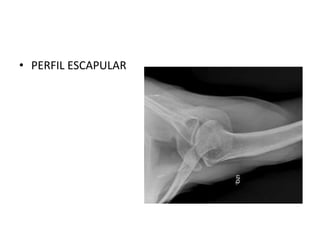

ESTUDIOS DIAGNOSTICOS

• AP DE HOMBRO

VERDADERA

• TRANSTORACICA

• PERFIL ESCAPULAR

• TAC

• RESONANCIA

MAGNETICA

ESTUDIOS DIAGNOSTICOS • APDE HOMBRO VERDADERA